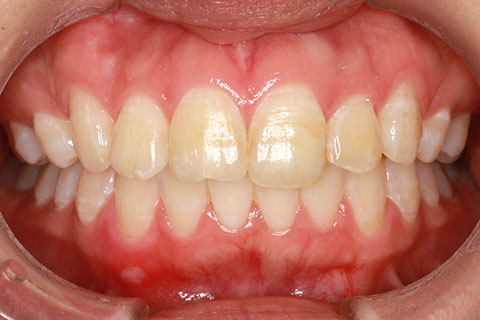

矯正期間24ヶ月

フルリンガル矯正1(上下の歯を舌側矯正で治療)

治療前

治療後

- 年齢・性別

- 33歳女性

- 治療期間

- 2年0ヶ月

- 抜歯

- 上顎4番抜歯。下顎5番欠損。

- 治療費

- 120万円(税込み)

- 備考

- フルリンガル矯正

- 治療内容

- 上顎前歯の叢生改善および下顎前歯の空隙閉鎖

- 施術の副作用(リスク)

- 装置が裏側について、目視ができないため、しっかりとブラッシングができているかどうかわかりにくい。